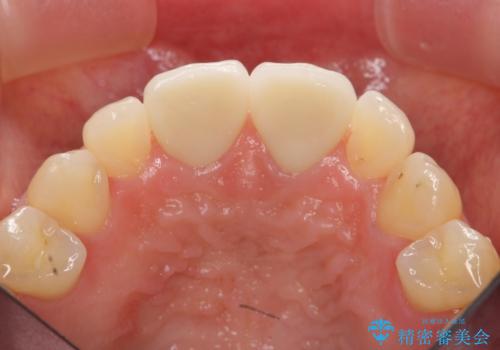

短期集中 前歯審美治療

- 32万円(仮歯・ファイバーコア・ジルコニアクラウンスペシャル×2)費用は治療当時の料金となります

ただ見えるクラウンを白くきれいにするのではなく、長期的な歯の予後を考えると根管治療・ファイバーコア築盛・精密な歯牙形成等クリアすべき条件は多々あると言えます。